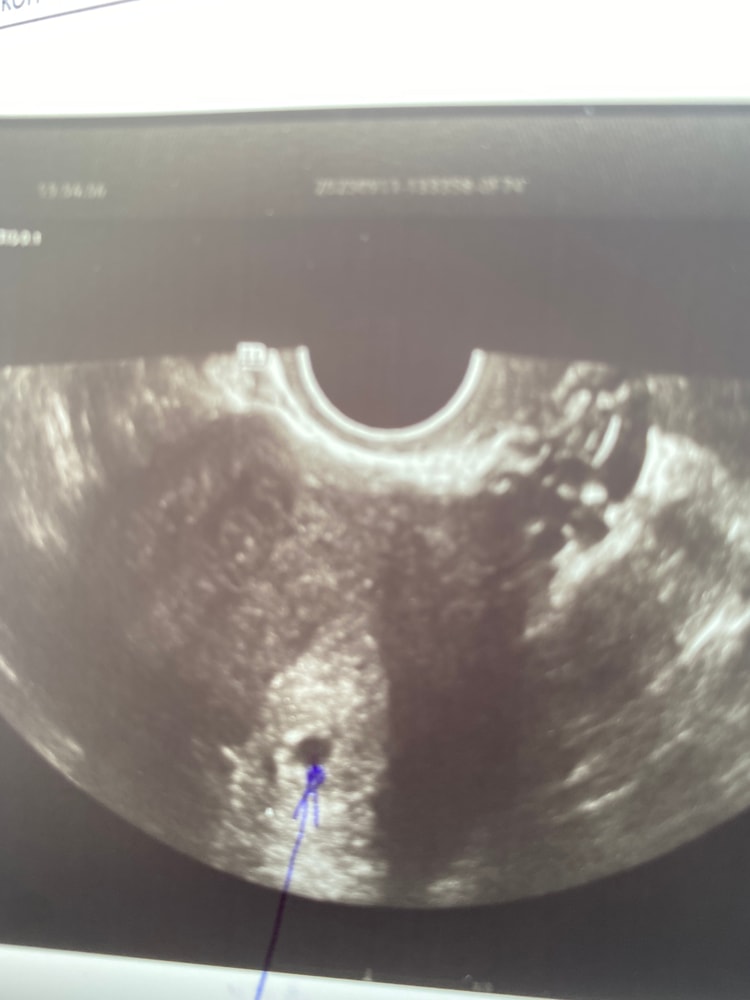

Первое узи ♥️

Поздравляю! Но мне кажется, что срок у вас меньше, на 6 акушерских уже жм хорошо видно и яйцо крупнее

Барабашка, вот и не знаю,по месячным считай 6 недель,а по узи 4,5 поставили 🤷🏽‍♀️надеюсь все хорошо

София, ну, судя по узи, овуляция была где-то 3 недели назад. А точнее 2,5 недели назад +-. Растите соответственно!